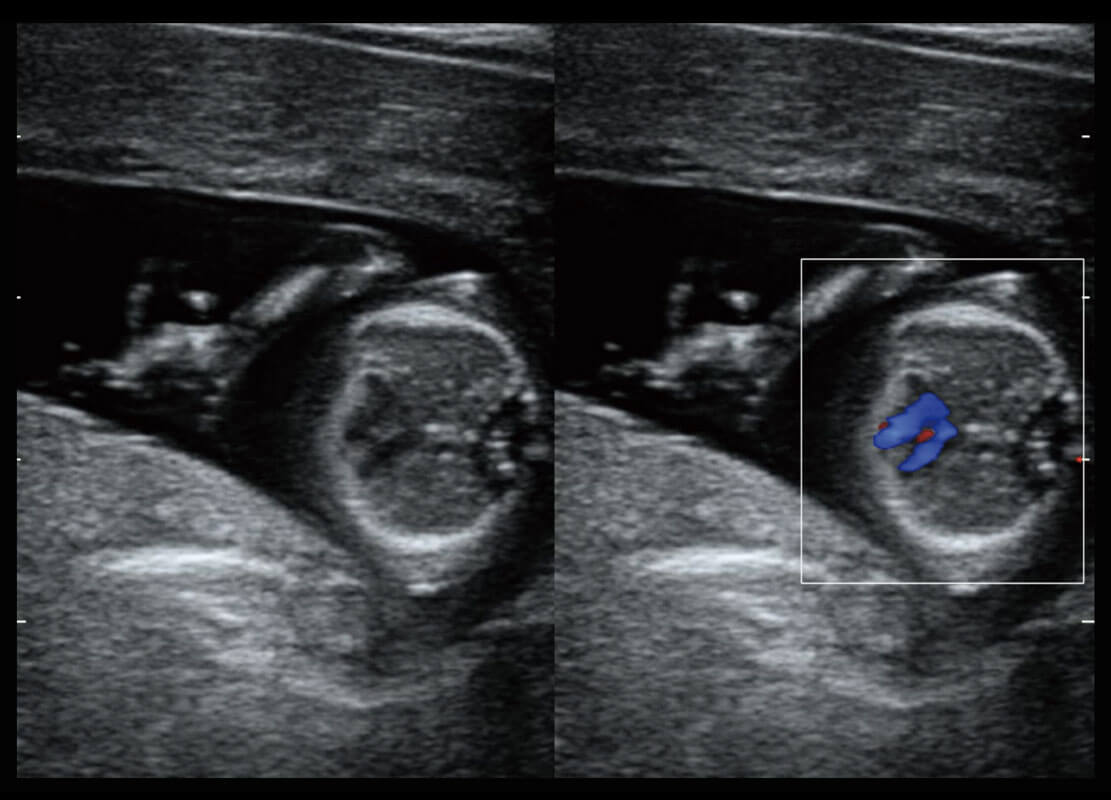

P60搭载宽频带线阵探头、宽景成像、弹性成像技术,为您提供乳腺应用方案。P60支持高频相控阵探头、线阵探头、腹部高频探头、腹部微凸探头等,丰富的探头群搭载敏感的彩色血流成像,适用于新生儿多种脏器检测要求,满足新生儿筛查需求。

乳腺导管癌

乳腺癌显微血流